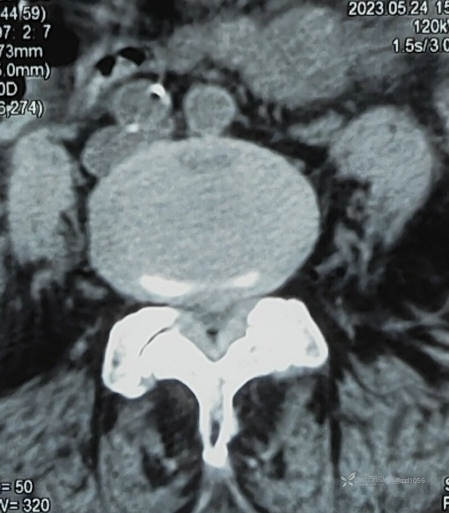

黄韧带肥厚

椎管狭窄

核磁结果L4/5狭窄明显,L5/S1突出存在,仔细查体,高度考虑左下肢L5根症状,其实患者也说不清楚,并且耳背😃